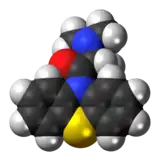

| IUPAC name

2-(Dimethylamino)-1-phenothiazin-10-ylpropan-1-one | |

| C17H18N2OS | |

| Molar mass | 298.40 g/mol |

Dimethylaminopropionylphenothiazine or 10-(alpha-dimethylaminopropionyl)phenothiazine is an antispasmodic.[1]